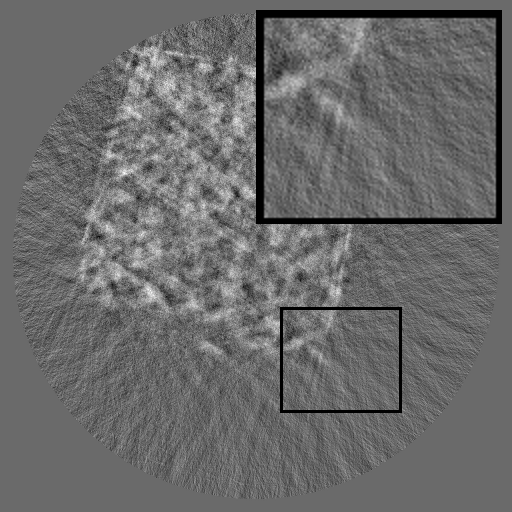

Figure 1: Comparisons of RGB, sinogram and their spectra. Unlike RGB images that have localized frequency components, sinograms exhibit structured spectral distributions due to the Radon transform.

Although inpainting methods have been extensively studied in the context of RGB images (Liu et al., 2024; Zhang et al., 2023; Ko and Kim, 2023; Deng et al., 2022; Lugmayr et al., 2022; Li et al., 2022; Suvorov et al., 2022), their applicability to X-ray sinograms remains relatively underexplored. Most RGB-based approaches rely on the assumption that missing regions can be locally inferred from surrounding pixels. However, this assumption does not readily hold for sinograms, where each pixel encodes an integrated projection value along an X-ray path, leading to globally coupled and highly entangled structures. Several studies have explored sinogram completion using U-Net-based (Zhao et al., 2018; Yao et al., 2024), GAN-based (Valat et al., 2023b; Xie et al., 2022) or Transformer-based (Jiaze et al., 2025) models, and some have incorporated periodicity or reconstruction-based constraints (Li et al., 2019c; Wagner et al., 2023). However, these methods remain largely spatial, focusing on pixel-wise interpolation or appearance realism, and fail to explicitly model the structured frequency domain or the governing physics of sinogram formation, which are fundamentally distinct from those of RGB images. As defined by the Radon transform (Radon, 1917), the detector and angle axes of a sinogram represent distinct physical dimensions, leading to highly directional and asymmetric spectral patterns (see Figure 1). These observations highlight the need to explicitly account for the frequency structure and physical consistency inherent to sinograms when performing data completion.